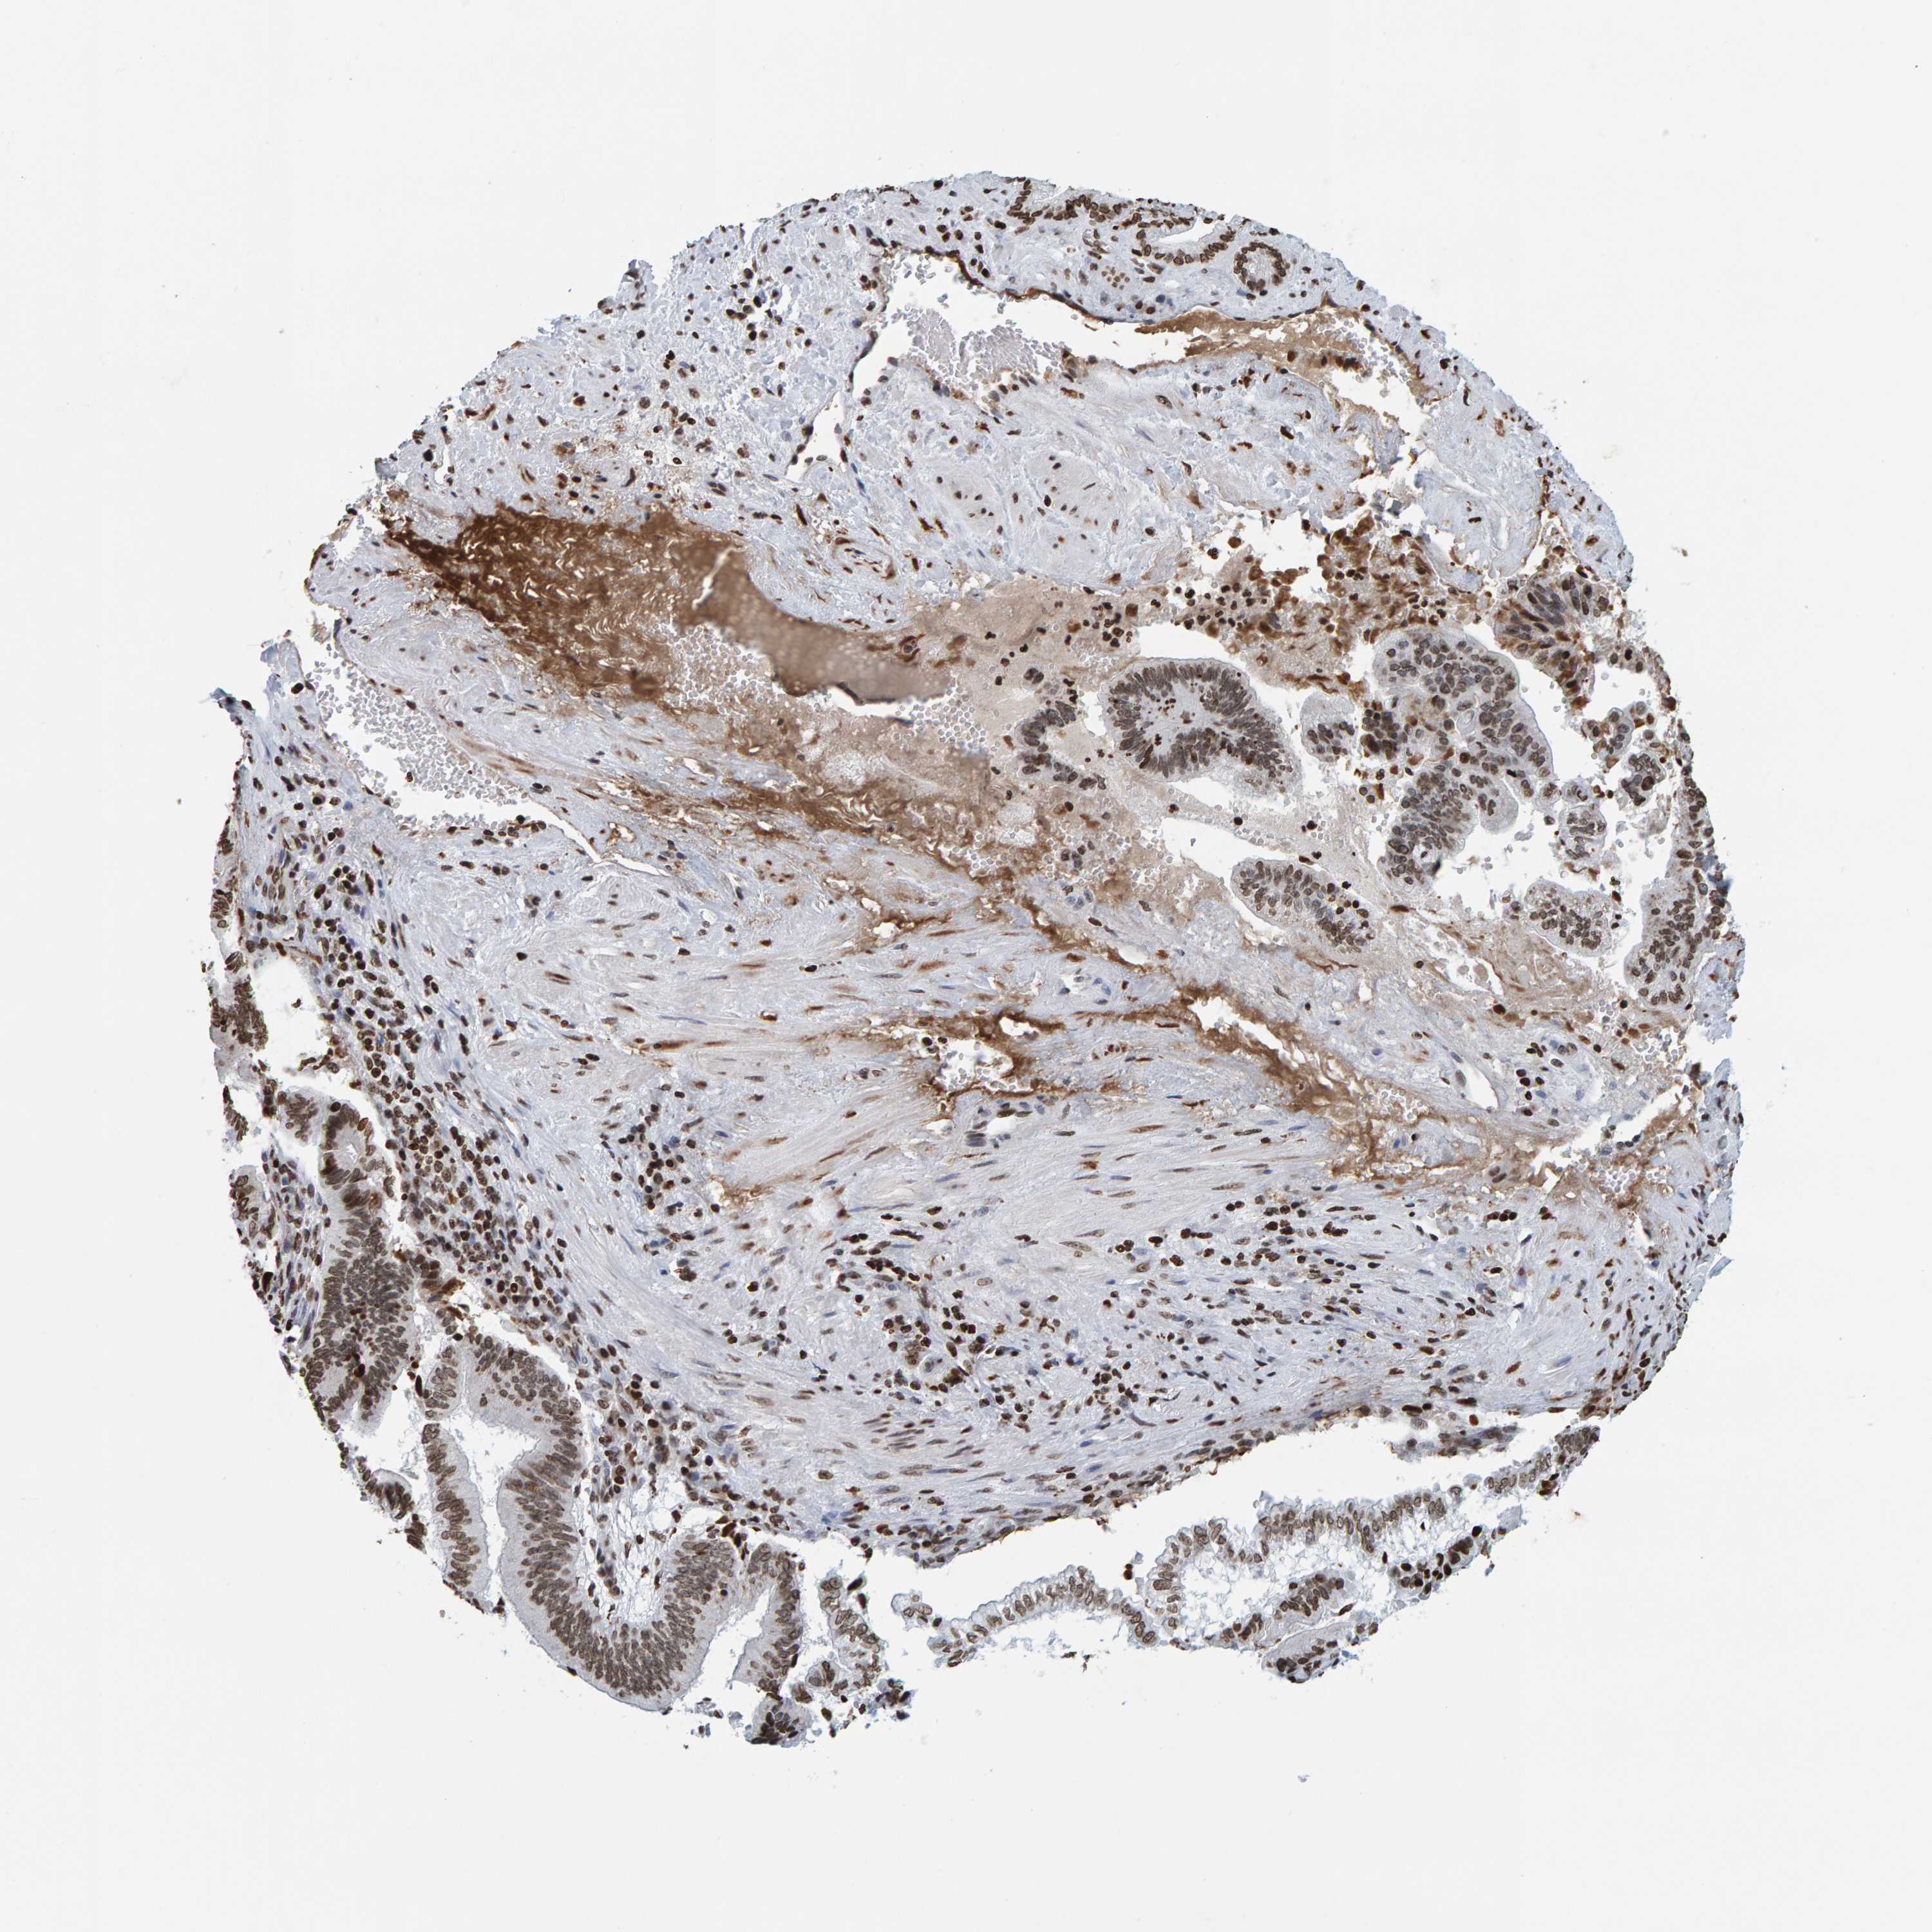

PANCREATIC CANCER - Protein expressioni

A mouse-over function shows sample information and annotation data. Click on an image to view it in a full screen mode. Samples can be filtered based on level of antibody staining by selecting one or several of the following categories: high, medium, low and not detected. The assay and annotation is described here.

Note that samples used for immunohistochemistry by the Human Protein Atlas do not correspond to samples in the TCGA dataset.

Antibody stainingi

Antibody staining in the annotated cell types in the current human tissue is reported as not detected, low, medium, or high, based on conventional immunohistochemistry profiling in selected tissues. This score is based on the combination of the staining intensity and fraction of stained cells.

Each image is clickable and will lead to virtual microscopy that enables deeper exploration of all samples and also displays staining intensity scores, fraction scores and subcellular localization as well as patient and tissue information for each sample.

Antibody HPA023378

Antibody CAB019269

Staining

High

Medium

Low

Not detected

Intensity

Strong

Moderate

Weak

Negative

Quantity

>75%

75%-25%

<25%

None

Location

Nuclear

Cytoplasmic/membranous

Cytoplasmic/membranous,nuclear

Adenocarcinoma, NOS

Adenocarcinoma, metastatic, NOS